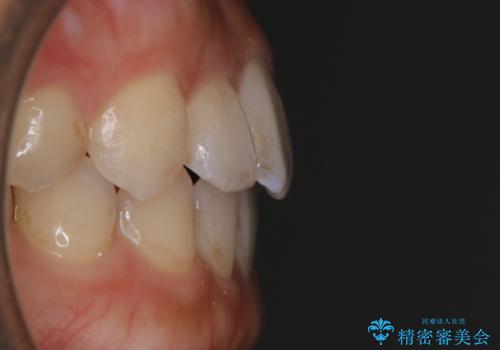

- 矯正治療を主訴にご来院されました。

すきっ歯と噛み合わせの治療をしたいとのことで、インビザラインを用いて矯正治療を行うこととなりました。

すきっ歯の場合、ガタつきを治したりするのに必要なスペースが最初から空いているため、そのスペースを利用して比較的短期間で効率よく治療を進めることが可能となります。

初診時の写真では一見噛み合わせには問題がないように見えても、実際に精密な検査を行うと改善すべき点が見つかる場合も多くあります。